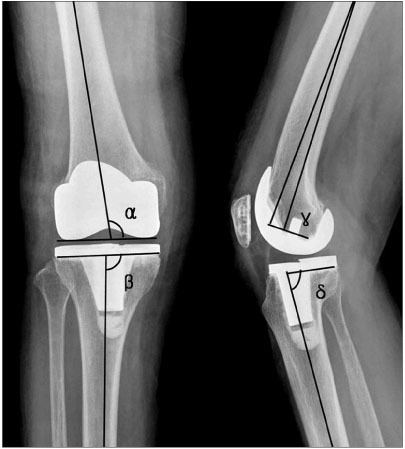

Indications for the use of this prosthesis?

the patient depicted had instability following CR knee and PCL rupture

Indications for the following prosthesis

Constrained hinge with rotating platform

Why was this prosthesis choosen?

Tumour Prosthesis